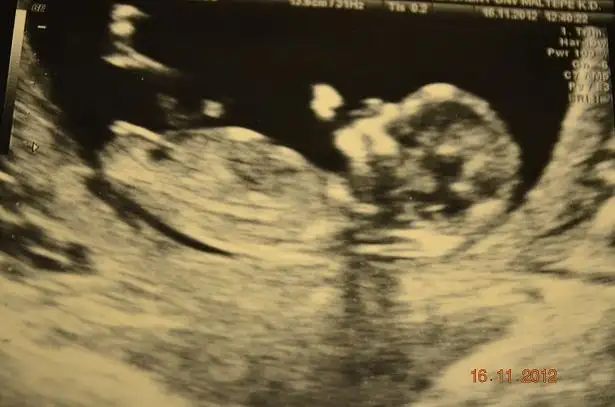

Eki Görüntüle 558237 12+3

Bunlarda internetten bulduğum kız olması beklenirken erkek doğan bebeklerin usgleri![]()